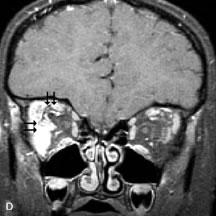

Fig. 21. A. T1-weighted MR scan demonstrates diffuse enlargement of both the superior rectus and levator palpebrae superioris muscles (single arrows). The involvement of the tendinous insertions and preseptal soft tissues (open arrows) as well as lack of involvement of other muscles helps differentiate this entity from thyroid-associated orbitopathy. B and C. Postcontrast fat-suppressed T1-weighted MR scans demonstrate extensive enhancement of the involved muscles as well as the preseptal (open arrows) and perinuscular tissues (double arrows).